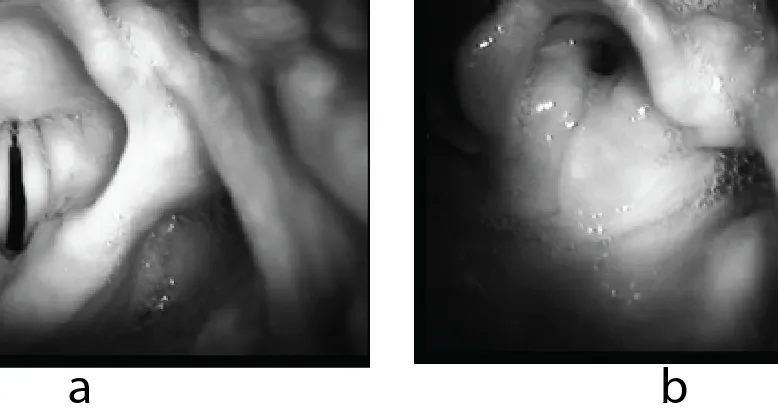

- Laryngospasm: Reflex glottic closure.

- Causes: Irritation (secretions, blood), light anesthesia, pain.

- Signs: Stridor, "rocking horse" breathing, ↓SpO₂.

- 📌 Mnemonic: Larson's maneuver, Oxygen (100%), Suction, Suxamethonium.

- Mgmt: 100% O₂, PPV, Larson's maneuver, deepen anesthesia (Propofol 10-30mg), Succinylcholine 0.1-1 mg/kg IV or 4-5 mg/kg IM.